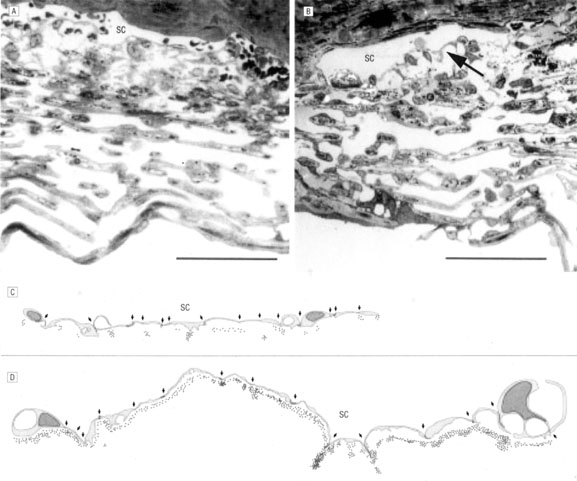

The ciliary epithelial cells have been subject to intensive study by light and electron microscopy. A striking feature is the interdigitation of the lateral surfaces of adjacent cells and the basal infoldings (Fig. 4), which are characteristic features of secretory epithelia concerned with fluid transport.14 The relation of the two epithelial cell layers is of importance because as the secreted aqueous is derived from an ultrafiltrate of blood in the stroma of the ciliary body, transport must occur across both layers. The double-layered ciliary epithelium itself is derived from anterior continuations of the retinal pigmented epithelium (forming the pigmented layer), and the neuroepithelium from which the retinal cells are derived (forming the nonpigmented layer). However, during embryogenesis, invagination of the neuroepithelium occurs, with the result that the apical surfaces of each cell layer in the ciliary epithelium face one another, while the basolateral surface of the nonpigmented layer faces directly into the posterior aqueous chamber. Conversely, the basolateral surface of the pigmented layer is tightly bound to the basement membrane. Cells of the pigmented epithelium contain many melanin granules. Gap junctions are present between the lateral interdigitations of the pigmented cells. Desmosomes also occur between the lateral interdigitations of the pigmented and nonpigmented epithelia and between their apical membranes.

Fig. 4. Schematic diagram of nonpigmented and pigmented epithelial cells. Note apices of cells facing each other. Basal infoldings (BI); basement membrane (BM); ciliary channels (CC); desmosomes (DES); fenestrated capillary endothelium (FE); gap junction (GJ); melanosome (MEL); mitochondrion (MIT); red blood cell (RBC); rough endoplasmic reticulum (RER); tight junction (TJ). (From Caprioli J: The ciliary epithelia and aqueous humor. In Hart M (ed): Adler's Physiology of The Eye, 9th ed, pp 228–247. St. Louis, Mosby Year-Book, 1992, with permission.)

The cells of the inner nonpigmented epithelium possess numerous intermediate-sized mitochondria, and the rough endoplasmic reticulum is particularly well developed, indicative of active protein synthesis. Small vacuoles may be present in large numbers near the apex of these cells. Occasionally, a few pigmented granules may be seen. Tight junctions are present in the lateral interdigitations between the nonpigmented cells (Fig. 4), thus forming a barrier for the passage of larger molecules between the cells. This important physiologic barrier, constituting part of the blood-aqueous barrier, is discussed further in a later section.